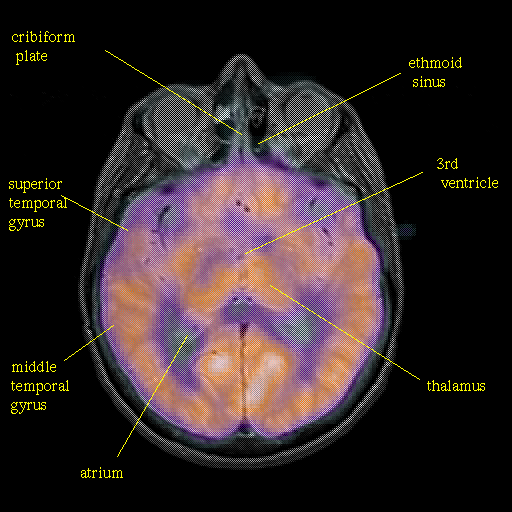

Pointers

Labeled